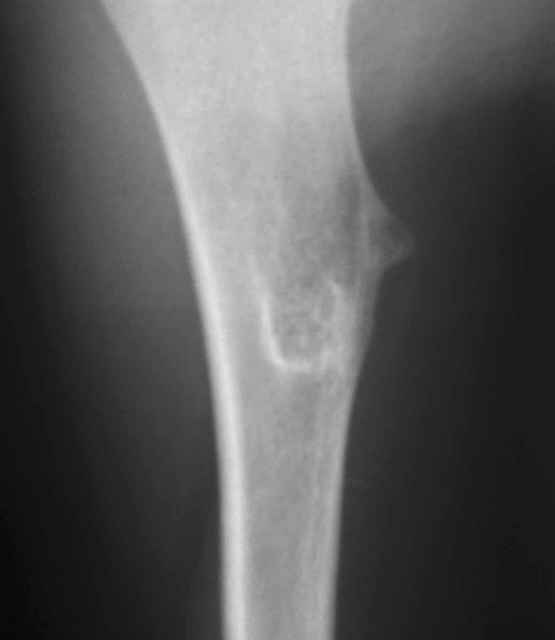

Энхондрома (?)

У 12-летнего мальчика образовалась припухлость на верхней трети плеча.

Рентгенобслежование выявило такую картину. Нельзя исключить энхондрому диафиза плечевой кости. Какую тактику лечения выбрать: экскохлеация или сегментарная резекция? Какие ортопедические центры, имеющие опыт лечения данной патологии, можно рекомендовать родителям мальчика для консультации и возможного, качественного, лечения? Спасибо.